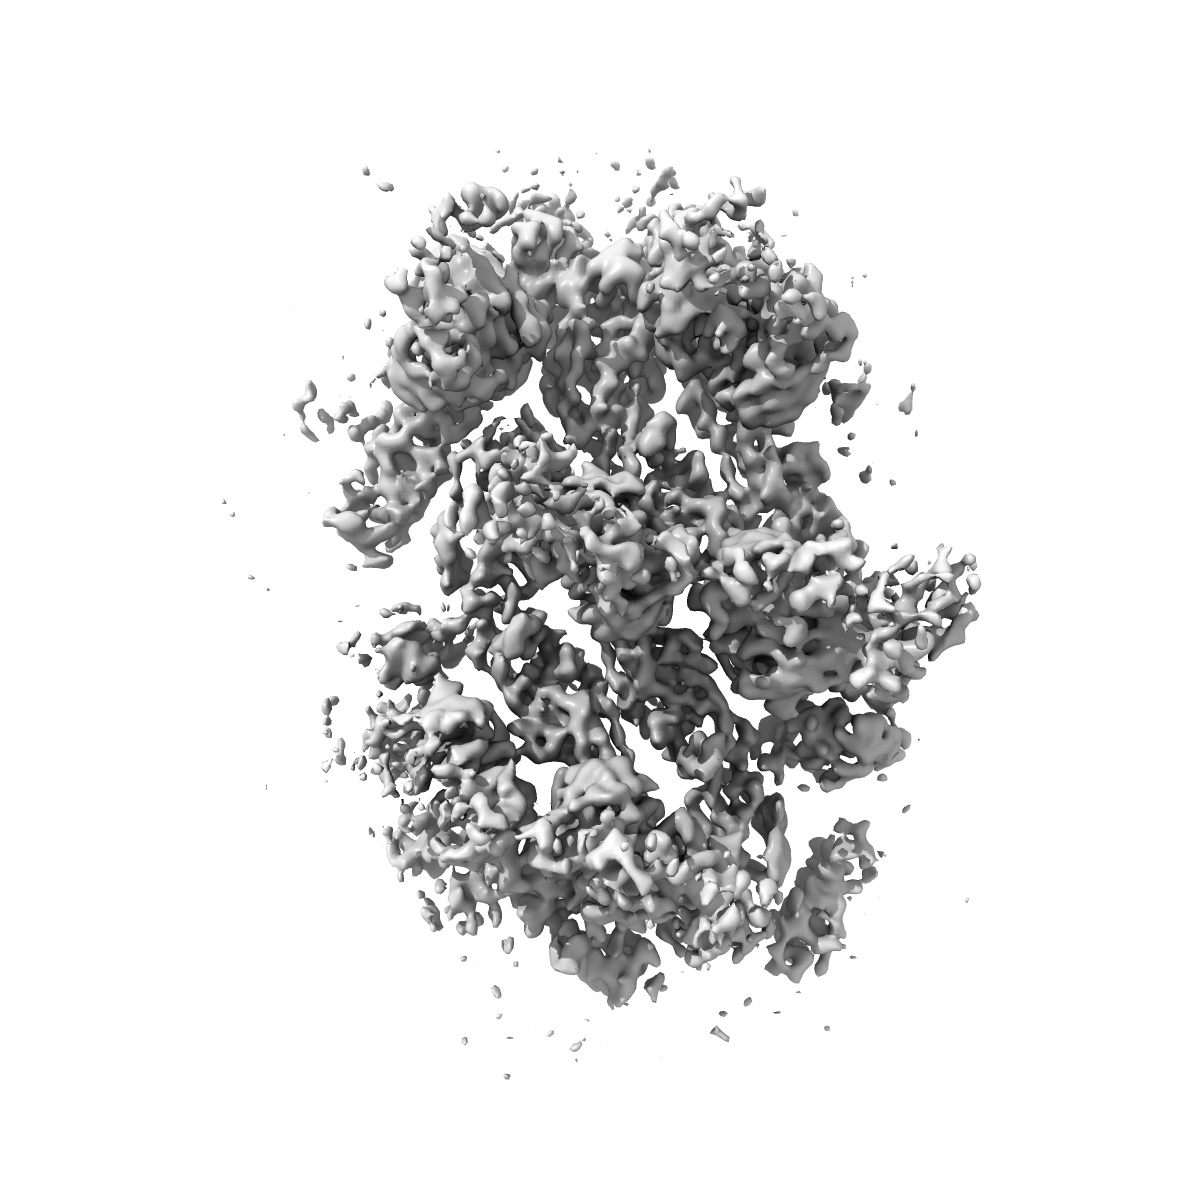

Envelope protein ASU of YFV-ES504 with YFV-17D DIII in complex with 2C9 Fab

Single-particle3.6 Å

Sample: YFV envelope protein expressed in the backbone of Binjari virus in complex with 2C9 Fab

Fitted models: 9b6w

A single residue in the yellow fever virus envelope protein modulates virion architecture and antigenicity.